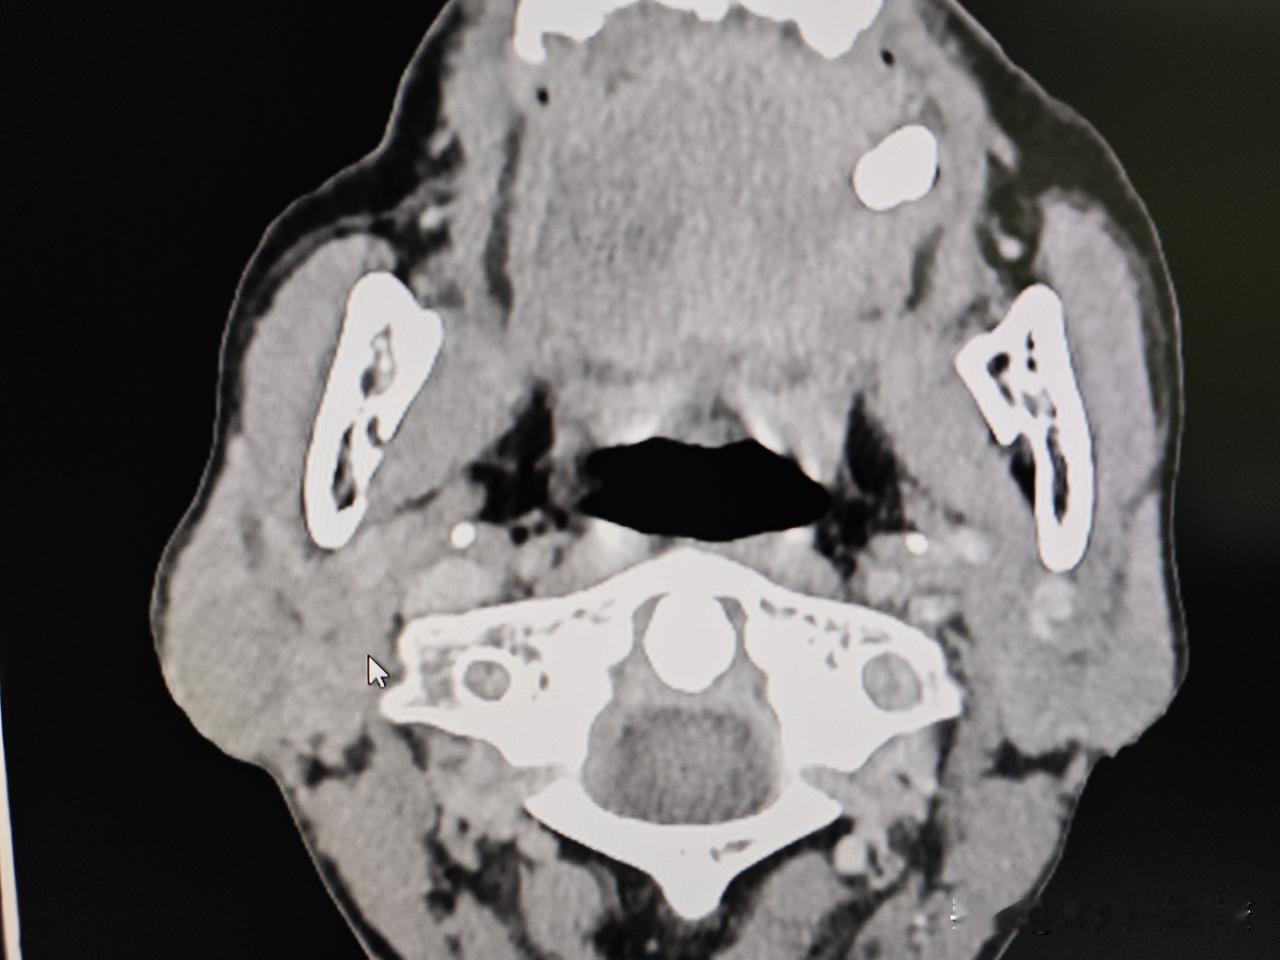

今天完成一例腮腺混合瘤手术切除病例分享, 腮腺混合瘤也算是头颈外科很常见疾病了,